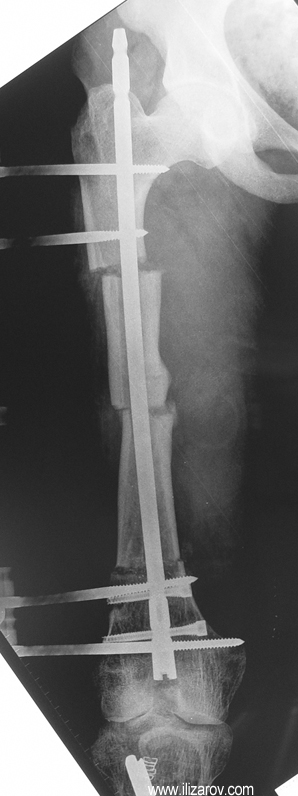

Hipofosfatemik raşitizmin neden olduğu bozukluk büyüme plağına çok yakın olduğu için büyük bir deformite ve ciddi dizilim bozukluğu ortaya çıkar. Bu nedenle cerrahi öncesi değerlendirmede sıklıkla birden çok deformite merkezi (CORA) bulunur ve deformitenin düzeltilmesi için birden çok seviyeden osteotomi yapılması gerekir. Deformitenin düzeltilmesi için en sık kullanılan yöntemler Ilizarov yöntemi ya da monolateral eksternal fiksatör kullanılarak akut ya da tedrici deformite düzeltilmesidir. Kliniğimizde uygulanan fiksatör yardımlı çivileme yönteminde deformite eksternal fiksatör kullanılarak akut olarak düzeltildikten sonra intramedüller çivi ile stabilizasyon sağlanmakta, uzatma yapılmayacaksa eksternal fiksatör cerrahi sona ermeden çıkartılmakta, uzatma yapılacaksa (çivi üzerinden uzatma) uzatma tamamlandıktan sonra fiksatör çıkartılmaktadır. Bu sayede tel dibi enfeksiyonu riski ortadan kalkmakta, hipofosfatemik raşitizm tedavisinde önemli sorunlar olan koreksiyon kaybı ve deformite nüksü önlenmekte, hastaya erken hareket verilerek tam yükle yürümesine izin verilmekte ve eksternal fiksatör süresi azaldığı için hasta konforu artmaktadır.

Vaka 3